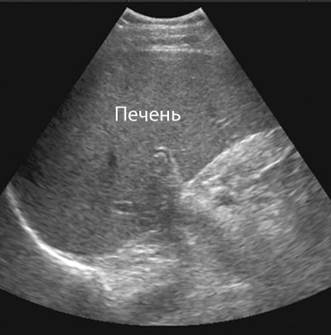

Құрсақ қуысы УДЗ:

Бауыр өлшемдері ұлғайған. Оң бөлігі қалыңдаған: 12,6 см , оң бөлігі, вертикальды қисық өлшемі (КВР): 15 см, оң бөлігі, ұзындығы:15 см, сол бөлімнің қалыңдығы: 7 см, биіктігі немесе сол бөлігінің кранио-каудальды өлшемі, (ККР) 10 см, барлық мүше ұзындығы: 18 см, мүше көлденеңі: 22,5 см, сагиттальды өлшемі:12 см. Контуры – айқын, тегіс, құрылымы – гомогенді, қақпа вена – эхонегативті, лентообразды түзілім, интенсивті есес ұсақ эхосигналдар бар, олардың арасында– эхонегативті кеңістік (мүшеде көп қантамырлар болғандықтан– өт және қантамырлық), қақпа венасының өзектері бауыр перифериясында орналасқан, құрылымы –интенсивтілігі әлсіз, ұсақ түйіршікті, бірақ – гомогенді. Көкбауыры ұлғайған, өлшемі: қиғаш кескенде —14 см, көлденең – 9 см, қалыңдығы – 6 см.

Жалпы өт өзегінің өлшемі— 8 мм, қақпа вена -11 мм.

Ұйқы безі. Ұйқы безі ұлғаймаған. Ұйқы безі вирсунг өзегі кеңеймеген. Паренхимасы біртекті, гомогенді, контуры айқын, тегіс. Құрсақ қуысы. Құрсақ қуысында бос сұйықтық бар. Лимфа түйіндері көрінбейді. Аортаның құрсақ бөлігі кеңеймеген.